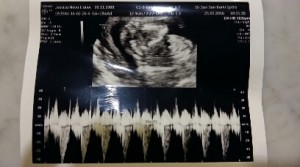

Today we went for our appointment, meeting our baby no. 2 who’s growing healthy and well. At this stage, baby no. 2 is slightly lighter than N. Our obgyn said that he’s 70% sure of the gender. I actually think that he’s 100% sure but to avoid disappointment, he told us to wait for another month. Oh well…